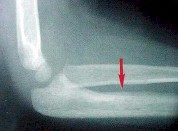

OSTEOSARCOMA:

Es el METAFISARIO más frecuente. Es el más común de los malignos!! Siempre cerca de las rodillas!! También en húmero proximal.

La forma telangiectásica es la más maligna. Siempre se llega tarde al diagnóstico!!

Da dolor nocturno y malestar. A veces debutan con fractura.

Es osteolítico u osteogénico o ambos, con permeación de las corticales.

Figura 21: osteosarcoma